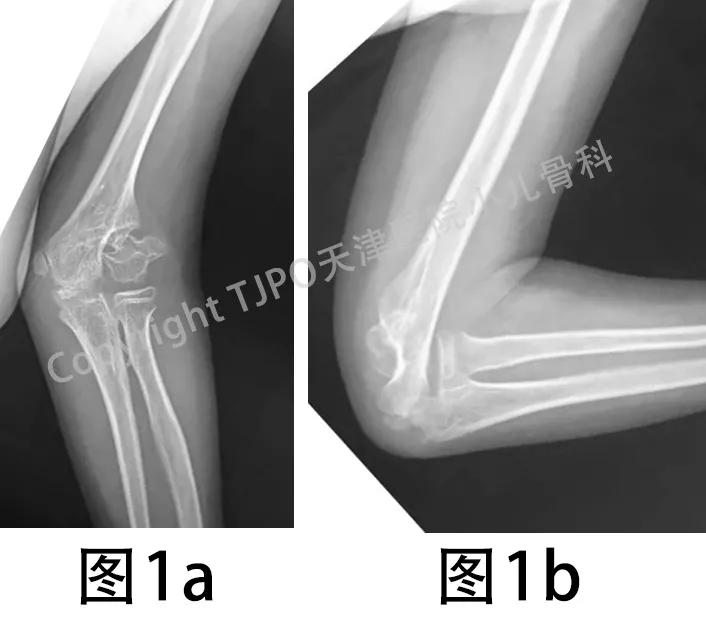

10岁男孩,2岁时曾摔伤左肘部致肿痛伴活动受限,当时未予检查治疗。后发现左肘关节变形且进行性加重,自诉9岁时出现左小指麻木,10岁时来诊,拍X线示:左肱骨外髁陈旧骨折不愈合,左肘外翻畸形(图1)。

图1a、图1b 左肱骨外髁陈旧骨折不愈合,左肘外翻